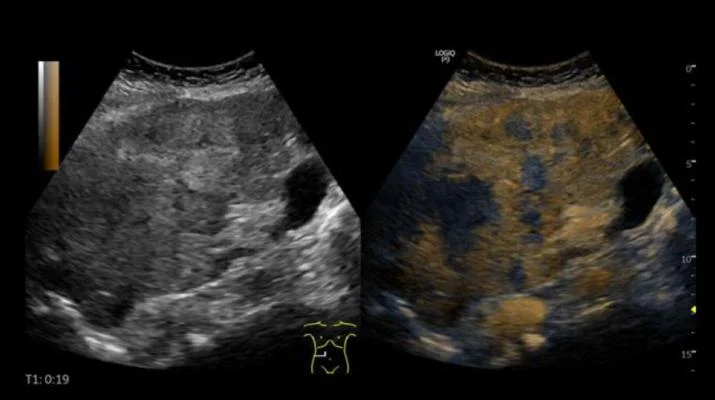

УЗИ с контрастным усилением ( CEUS ) является более точным и надежным, чем МРТ, для исследования определенных узлов печени и почек, согласно двум новым исследованиям, опубликованным в Journal of Ultrasound in Medicine (JUM) и отмеченным Международным контрастным ультразвуком. Общество (ICUS).

CEUS — это неинвазивный инструмент визуализации, который безопасно и регулярно используется во всем мире для выявления и характеристики рака, диагностики сердечно-сосудистых заболеваний, мониторинга хронических желудочно-кишечных заболеваний и мониторинга терапии.

Ультразвуковые контрастные вещества вводятся внутривенно для улучшения изображений, полученных при ультразвуковом сканировании, что позволяет визуализировать аномальные микрососудистые картины кровотока в режиме реального времени.

«Кроме того, CEUS позволяет улучшить визуализацию паттернов усиления в режиме реального времени, толщина тонкого среза CEUS позволяет оценивать небольшие узелки, многоплоскостная визуализация позволяет улучшить визуализацию и подтверждение усиления, а во время одного и того же обследования можно использовать несколько доз. чтобы дать возможность тщательно отобразить поражение», — сказал доктор Барр.

Она сказала, что ее исследование показало, что CEUS обеспечивает более высокую чувствительность по сравнению с МРТ (81% против 64%) для диагностики злокачественных новообразований без ущерба для специфичности (92% против 93%). Кроме того, CEUS с большей вероятностью, чем МРТ, воспроизвел и охарактеризовал узелок, обнаруженный при скрининге (97% против 78,5%).